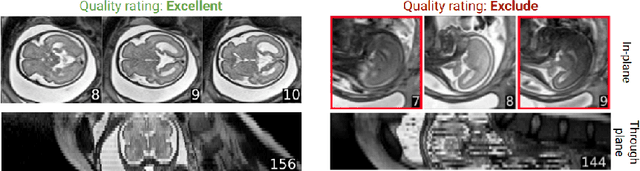

Abstract:Fetal brain MRI is becoming an increasingly relevant complement to neurosonography for perinatal diagnosis, allowing fundamental insights into fetal brain development throughout gestation. However, uncontrolled fetal motion and heterogeneity in acquisition protocols lead to data of variable quality, potentially biasing the outcome of subsequent studies. We present FetMRQC, an open-source machine-learning framework for automated image quality assessment and quality control that is robust to domain shifts induced by the heterogeneity of clinical data. FetMRQC extracts an ensemble of quality metrics from unprocessed anatomical MRI and combines them to predict experts' ratings using random forests. We validate our framework on a pioneeringly large and diverse dataset of more than 1600 manually rated fetal brain T2-weighted images from four clinical centers and 13 different scanners. Our study shows that FetMRQC's predictions generalize well to unseen data while being interpretable. FetMRQC is a step towards more robust fetal brain neuroimaging, which has the potential to shed new insights on the developing human brain.

Abstract:Quality control (QC) has long been considered essential to guarantee the reliability of neuroimaging studies. It is particularly important for fetal brain MRI, where large and unpredictable fetal motion can lead to substantial artifacts in the acquired images. Existing methods for fetal brain quality assessment operate at the \textit{slice} level, and fail to get a comprehensive picture of the quality of an image, that can only be achieved by looking at the \textit{entire} brain volume. In this work, we propose FetMRQC, a machine learning framework for automated image quality assessment tailored to fetal brain MRI, which extracts an ensemble of quality metrics that are then used to predict experts' ratings. Based on the manual ratings of more than 1000 low-resolution stacks acquired across two different institutions, we show that, compared with existing quality metrics, FetMRQC is able to generalize out-of-domain, while being interpretable and data efficient. We also release a novel manual quality rating tool designed to facilitate and optimize quality rating of fetal brain images. Our tool, along with all the code to generate, train and evaluate the model will be released upon acceptance of the paper.